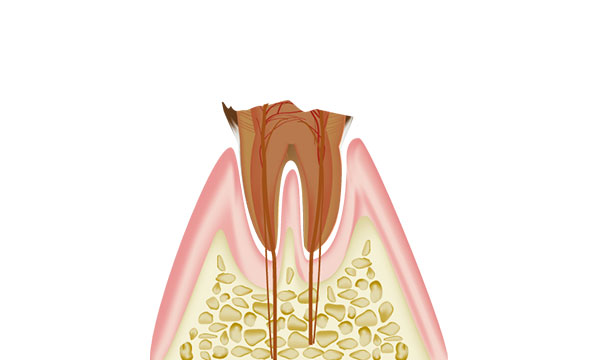

虫歯で歯が崩壊します。神経は細菌に感染して死んでしまいます。 細菌が溜まり根の先に膿を作ります。 ここまで進行すると神経が死んでいるため痛みを感じない事が多いですが、膿が溜まる事で痛みがでる場合もあります。 治療方法は根の治療か抜歯になります。